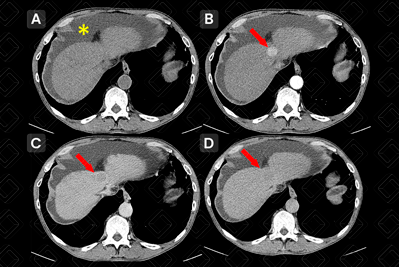

Texto alternativo para a imagem Créditos: Dra. Elazir Mota - Rio de Janeiro/RJ

Descrição da figura: Tomografia computadorizada do abdome, estudo com contraste venoso, em bomba injetora. Em A , estudo sem contraste, sendo difícil caracterizar a lesão (isodensa ao parênquima). Em B , na fase arterial, vemos nódulo hipoervascularizado (seta vermelha) no domo hepático. Em C e D , observamos lavagem ( wash out ) da lesão – consideramos que houve wash out quando a lesão fica mais hipodensa que o parênquima. No asterisco amarelo, observa-se a ascite.

• Tomografia computadorizada (TC) do abdome: É fundamental o uso de bomba injetora para otimizar o estudo da dinâmica de impregnação do meio de contraste venoso. O nódulo tumoral típico é hipodenso, no estudo sem contraste, com impregnação intensa em mais de 50% da sua área na fase arterial, configurando hipervascularização, e exibe rápida lavagem do contraste na fase portal (figura acima) ;